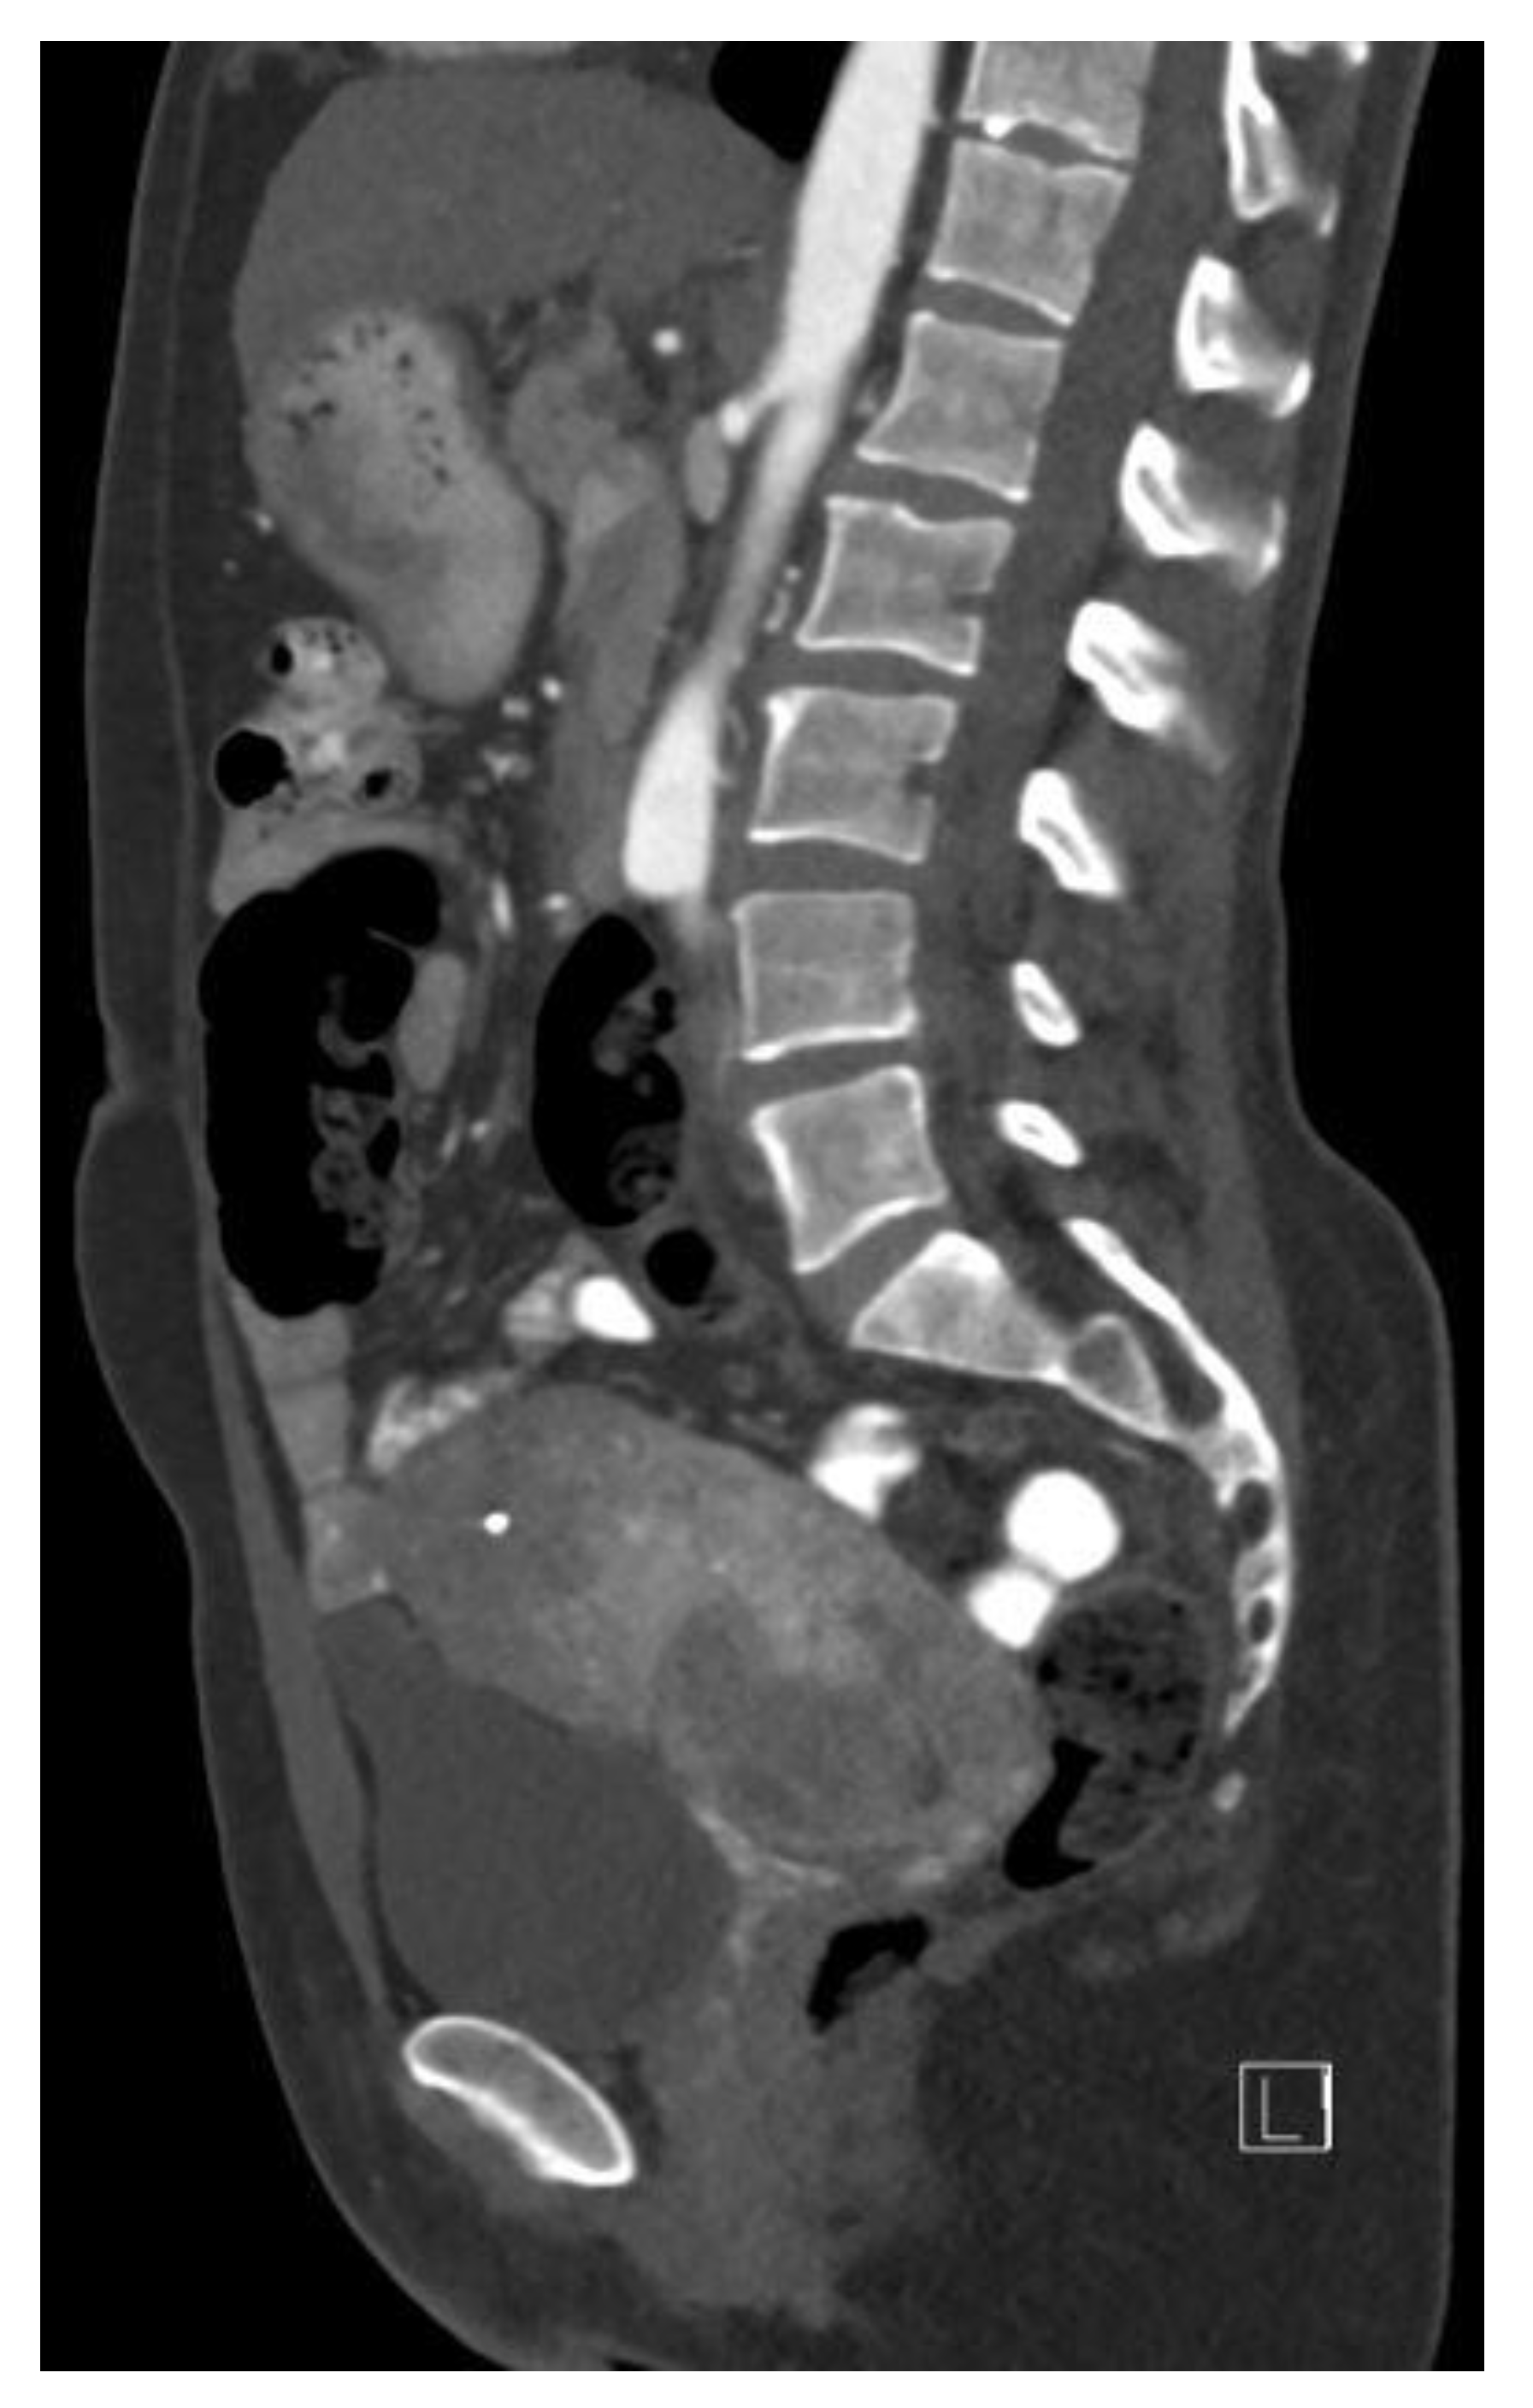

2.1. Clinical Findings